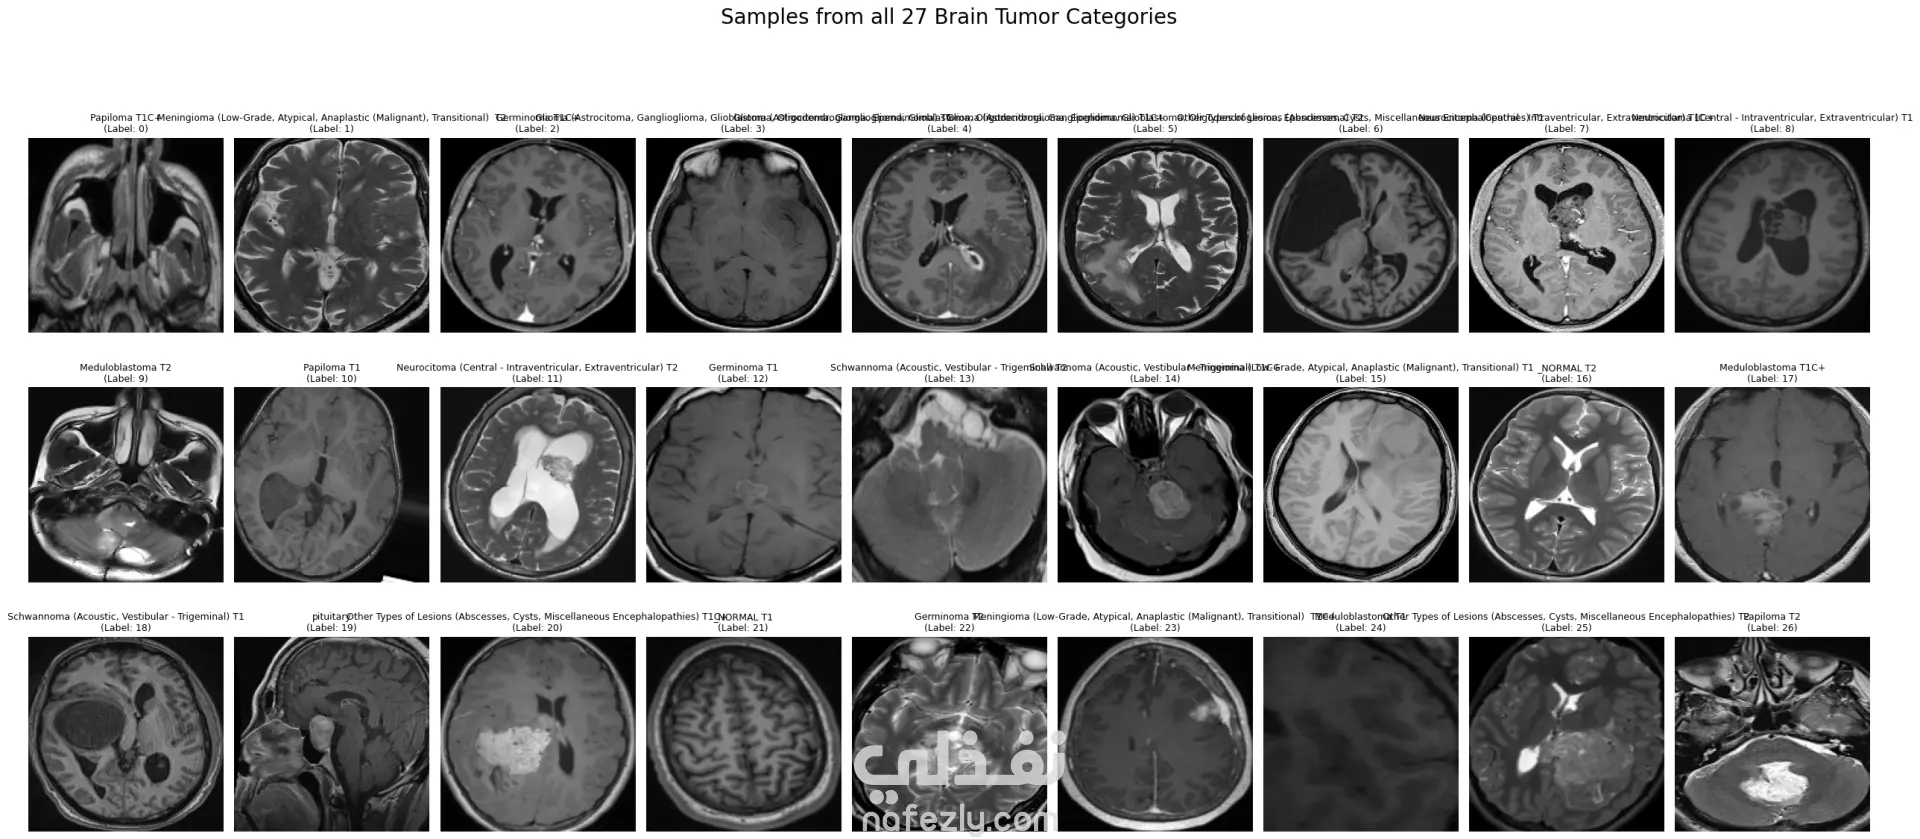

الوصف: قمت بتطوير نموذج تعلم عميق (CNN) قادر على التمييز بين 27 فئة مختلفة من الأورام والحالات الطبيعية بدقة تصل إلى 93%. شمل المشروع مراحل معالجة البيانات الضخمة، تنظيفها وموازنتها، وتصميم معمارية مخصصة لضمان الكفاءة العالية وتقليل استهلاك الذاكرة. المميزات التقنية: دقة استثنائية: حقق النموذج دقة تصل إلى 93% على بيانات التحقق (Validation Accuracy). معالجة البيانات الضخمة: تم العمل على قاعدة بيانات ضخمة، مع تطبيق استراتيجيات موازنة البيانات (Data Balancing) لضمان عدم انحياز الموديل. معمارية مخصصة: تم تصميم شبكة CNN تدعم تقنيات Batch Normalization لتسريع التعلم و Global Average Pooling لتقليل استهلاك الذاكرة وضمان استقرار النموذج. معالجة الصور: استخدام تقنيات OpenCV لقص الصور (Cropping) وإزالة الهوامش غير الضرورية لتركيز الموديل على منطقة الورم فقط. الأدوات والتقنيات المستخدمة: لغة البرمجة: Python. المكتبات الأساسية: TensorFlow / Keras. معالجة الصور: OpenCV & PIL. تحليل النتائج: Scikit-learn (Confusion Matrix & Classification Report). البيئة البرمجية: Google Colab (GPU Acceleration). النتائج المحققة: نموذج قادر على التعرف على أنواع نادرة من الأورام بدقة عالية. تقرير فني يوضح أداء الموديل لكل فئة (Precision & Recall). ملف نموذج جاهز للنشر (Deployment) بصيغة keras الحديثة. يمكنكم الاطلاع على الكود المصدري كاملاً والرسوم البيانية لتقييم أداء النموذج عبر رابط GitHub المرفق، كما يتوفر رابط تحميل النموذج المدرب داخل ملف الشرح.